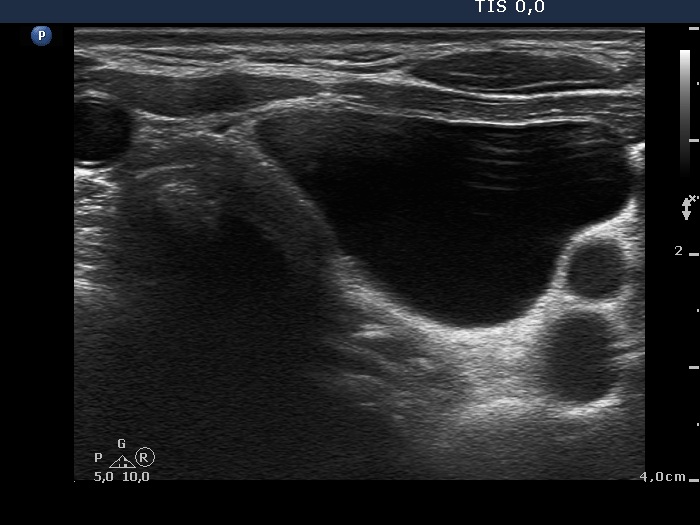

Right lobe, longitudinal scan

Under the left thyroid lobe, transverse scan. There is a cystic mass.